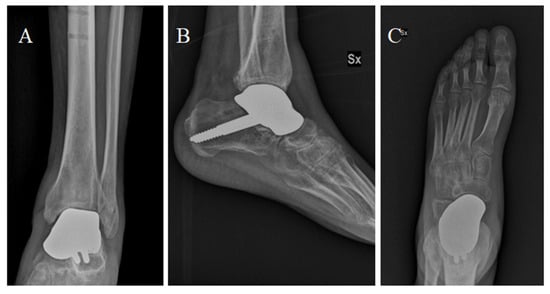

Figure 4.

Total talar replacement with subtalar fixation, post-operatory anteroposterior (A) and latero-lateral (B) X-ray.

Percutaneous Achilles tendon lengthening was performed to improve ankle dorsiflexion. After surgery, a plaster cast was applied for 3 weeks. After 3 weeks, partial weight bearing was allowed, with full weight bearing within 9 weeks of surgery. We decided to examine the patient at 1, 2, 4, 6, and 12 months after surgery, and then once a year (Figure 5). The patient was satisfied with the outcome of the surgery and showed good functional results: At 6 months, he presented an AOFAS (American Orthopedic Foot and Ankle Society Score) of 86 and an NRS (Numeric Rating Scale) of 2. The sagittal range of motion (ROM) was >30°. The patient satisfaction as well as the clinical scores were retained at the 12-month follow-up.

Figure 5.

Anterior-posterior (A), dorsoplantar (B) and latero-lateral (C) projections showing the implant at the 6-month follow-up after surgery.